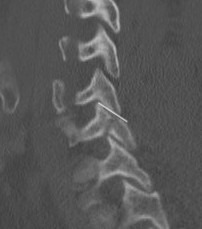

< 40% of the lateral mass

Superior articular facet fracture approximately 50% of the lateral mass